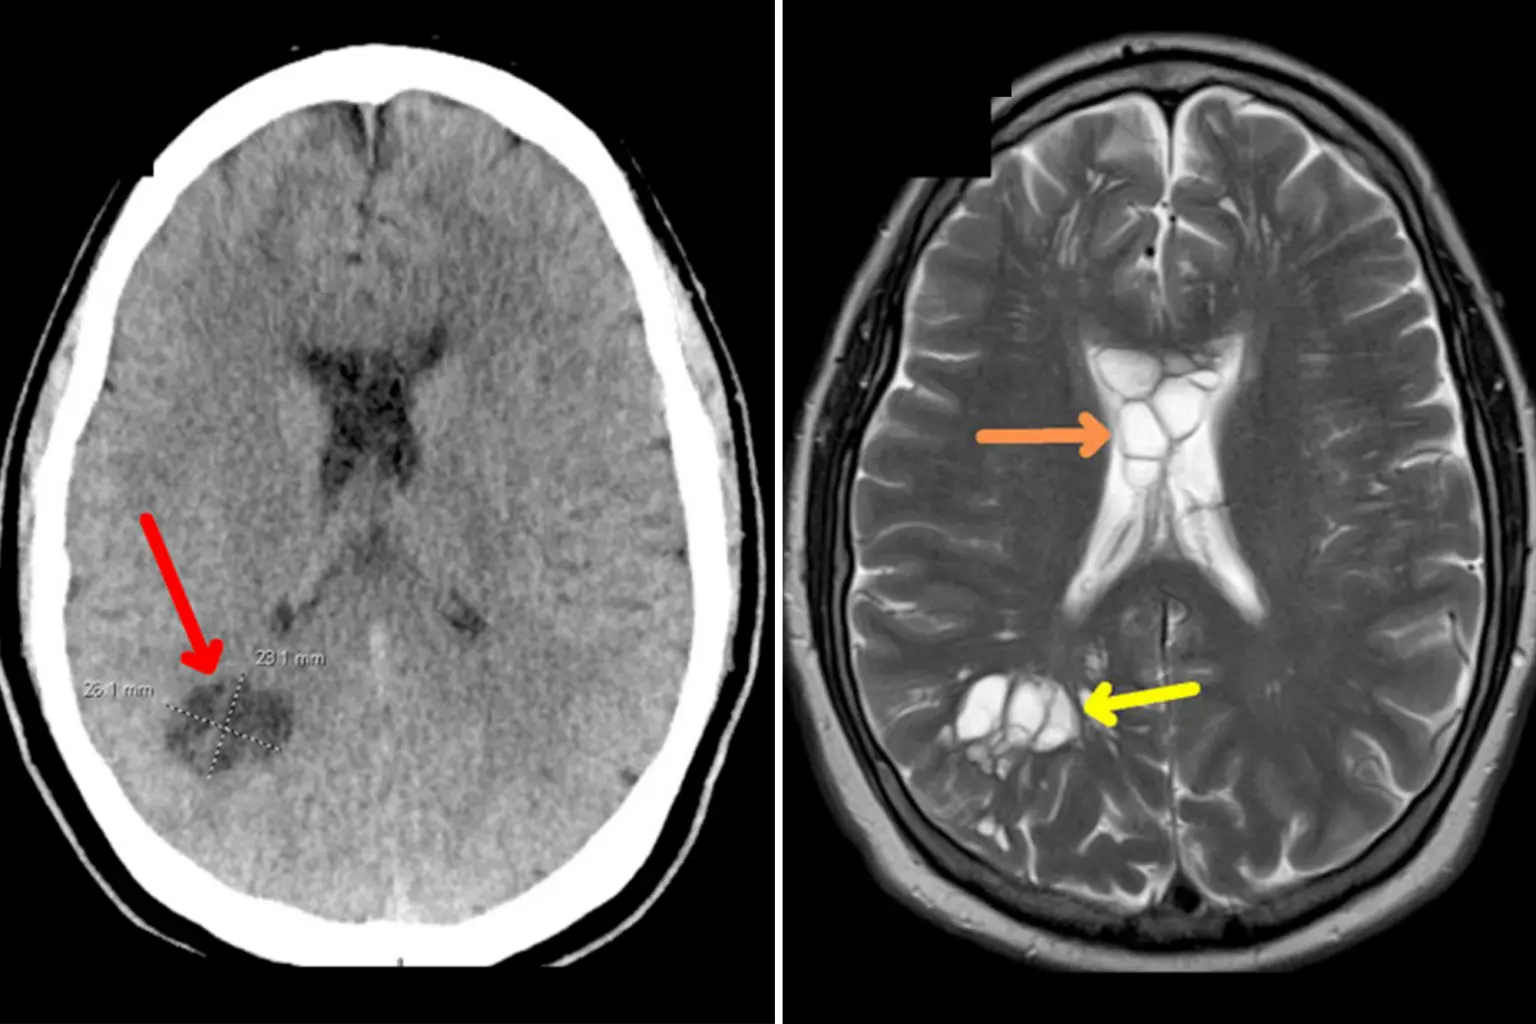

Άφωνοι έμειναν οι γιατροί στη Φλόριντα των ΗΠΑ με αυτό που ανακάλυψαν σε 52χρονο ασθενή. Ο άνδρας, που πιστεύεται ότι έπασχε από σοβαρές ημικρανίες, αντιμετώπιζε στην πραγματικότητα μια παράξενη μόλυνση από κεστοειδή σκώληκα στον εγκέφαλό του που προκλήθηκε από την κατανάλωση κακοψημένου μπέικον.

Ο ασθενής, η περίπτωση του οποίου δημοσιεύτηκε πρόσφατα στο American Journal of Case Reports, παραπονιόταν επί εβδομάδες ότι είχε έντονους πονοκεφάλους για διάστημα τεσσάρων μηνών μετά την κατανάλωση του μολυσμένου προϊόντος από χοιρινό.

Αυτός ο συνδυασμός παραγόντων οδήγησε σε μια περίπτωση νευροκυστικέρκωσης. Είναι ο επιστημονικός όρος για έναν παράσιτο που γεννά αυγά τα οποία μολύνουν διάφορες περιοχές του σώματος.  Μάλιστα, η νευροκυστικέρκωση μπορεί να είναι μεταδοτική.

Στην συγκεκριμένη περίπτωση, ο ασθενής εκτός από το οίδημα, ανέπτυξε κύστεις και στις δύο πλευρές του εγκεφάλου του. Αργότερα, αυτό αποδείχθηκε ότι προκλήθηκε από τo παράσιτο (κεστοειδής σκώληκας) που είχε γεννήσει αυγά μέσα στον εγκέφαλο του άνδρα.

Ο ασθενής θεραπεύτηκε με αλβενδαζόλη, το οποίο οδήγησε σε βελτίωση μετά από δύο εβδομάδες. Η αλβενδαζόλη είναι ένα φάρμακο που χρησιμοποιείται για τη θεραπεία μιας ποικιλίας παρασιτικών ελμινθικών λοιμώξεων.